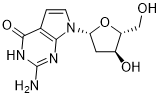

馬鞍山致研生物醫(yī)藥科技有限公司成立于馬鞍山市鄭浦港新區(qū)現(xiàn)代產(chǎn)業(yè)園。公司專(zhuān)注于生物小分子、醫(yī)藥中間體相關(guān)產(chǎn)品的研發(fā)和生產(chǎn),產(chǎn)品主要包括DNA亞磷酰胺單體、RNA亞磷酰胺單體、特殊單體以及按照客戶(hù)要求定制的RNA和DNA,并且公司提供定制合成等方面的研究服...

馬鞍山致研生物醫(yī)藥科技有限公司成立于馬鞍山市鄭浦港新區(qū)現(xiàn)代產(chǎn)業(yè)園。公司專(zhuān)注于生物小分子、醫(yī)藥中間體相關(guān)產(chǎn)品的研發(fā)和生產(chǎn),產(chǎn)品主要包括DNA亞磷酰胺單體、RNA亞磷酰胺單體、特殊單體以及按照客戶(hù)要求定制的RNA和DNA,并且公司提供定制合成等方面的研究服...